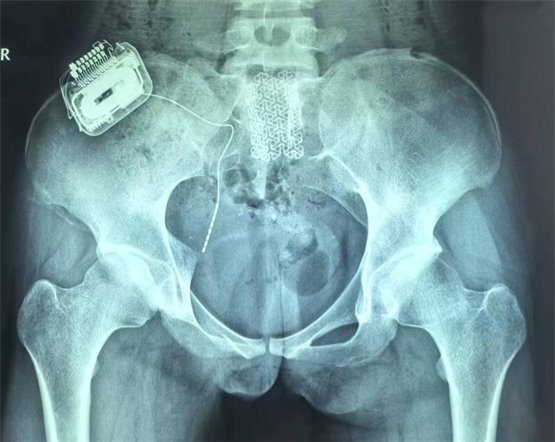

鉴于一期手术的良好疗效,患者家属决定进行二期永久植入,将骶神经电极及脉冲发生器永久性植入患者体内。二期手术后,患者白天已经无漏尿,夜间偶有遗尿(目前仍在调整过程中,希望通过调整合适的刺激参数,后续能够得到更好的改善);排尿费力感减轻(术前为点滴状,现尿线变粗,最大排尿量达220ml);肛门周围已恢复部分感觉,整体改善非常显著。

图4为骶神经调控术后骨盆正位片